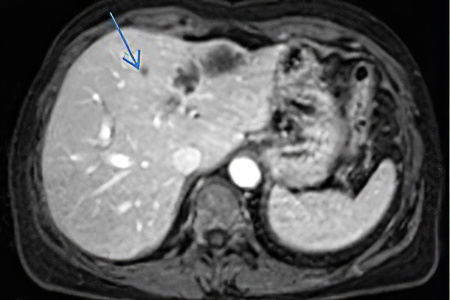

У 95% пациентов первичные отдалённые метастазы возникают в печени. В этом случае орган увеличивается в размерах и становится более плотным, что может вызывать дискомфорт и тяжесть в правом подреберье. С увеличением числа метастазов происходит замещение печёночной ткани, что нарушает её функции и может приводить к желтушности кожи.

Метастазы прямой кишки